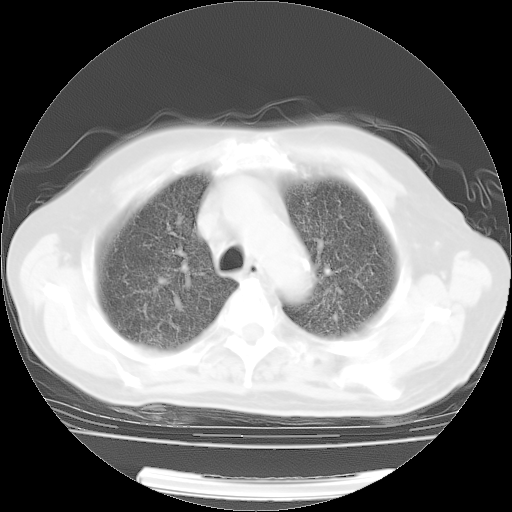

4月28日肺部CT——再次出现类似去年5月9日——透光度降低,(影像科认为)“间质性”改变。

4月28日肺部CT——再次出现类似去年5月9日——透光度降低,“间质性”改变。